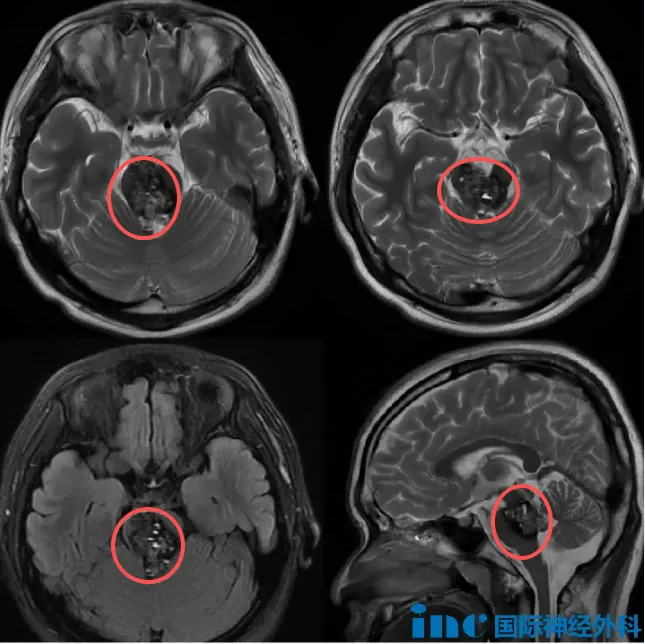

16岁的少年,被诊断出一个巨大的脑干海绵状血管瘤。复杂的病情令许多医生头疼,病灶不仅体积巨大,内部还伴随着出血,即使是巴教授,在看到核磁后也解释道:“一些其他的病人,如果有多发的海绵状血管瘤,通常会散落在大脑很多地方,也许脑干中只有1-2个病灶,但是这个孩子所有的病灶都在脑干内。”

脑干作为生命中枢,要想在这个区域切除一个肿瘤已经实属不易,更何况是如豆腐渣般遍布的大大小小的病灶。除此之外,这个海绵状血管团还占据中脑,甚至从后往前将桥脑“截断”,十分难缠。